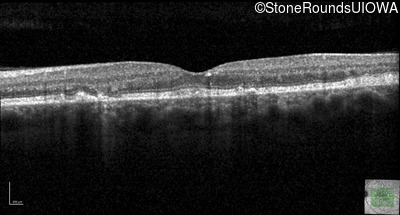

Optical Coherence Tomography - Left - 20/32 sc

Exemplar / OCT Stack